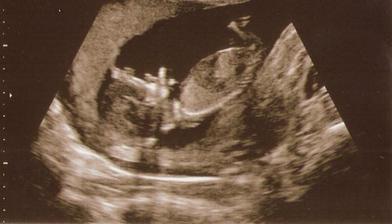

Naše milované miminko

v červnu 2010 se nám narodí naše první mimi..Jsme moc šťastní. A bude to malá princezna!!!